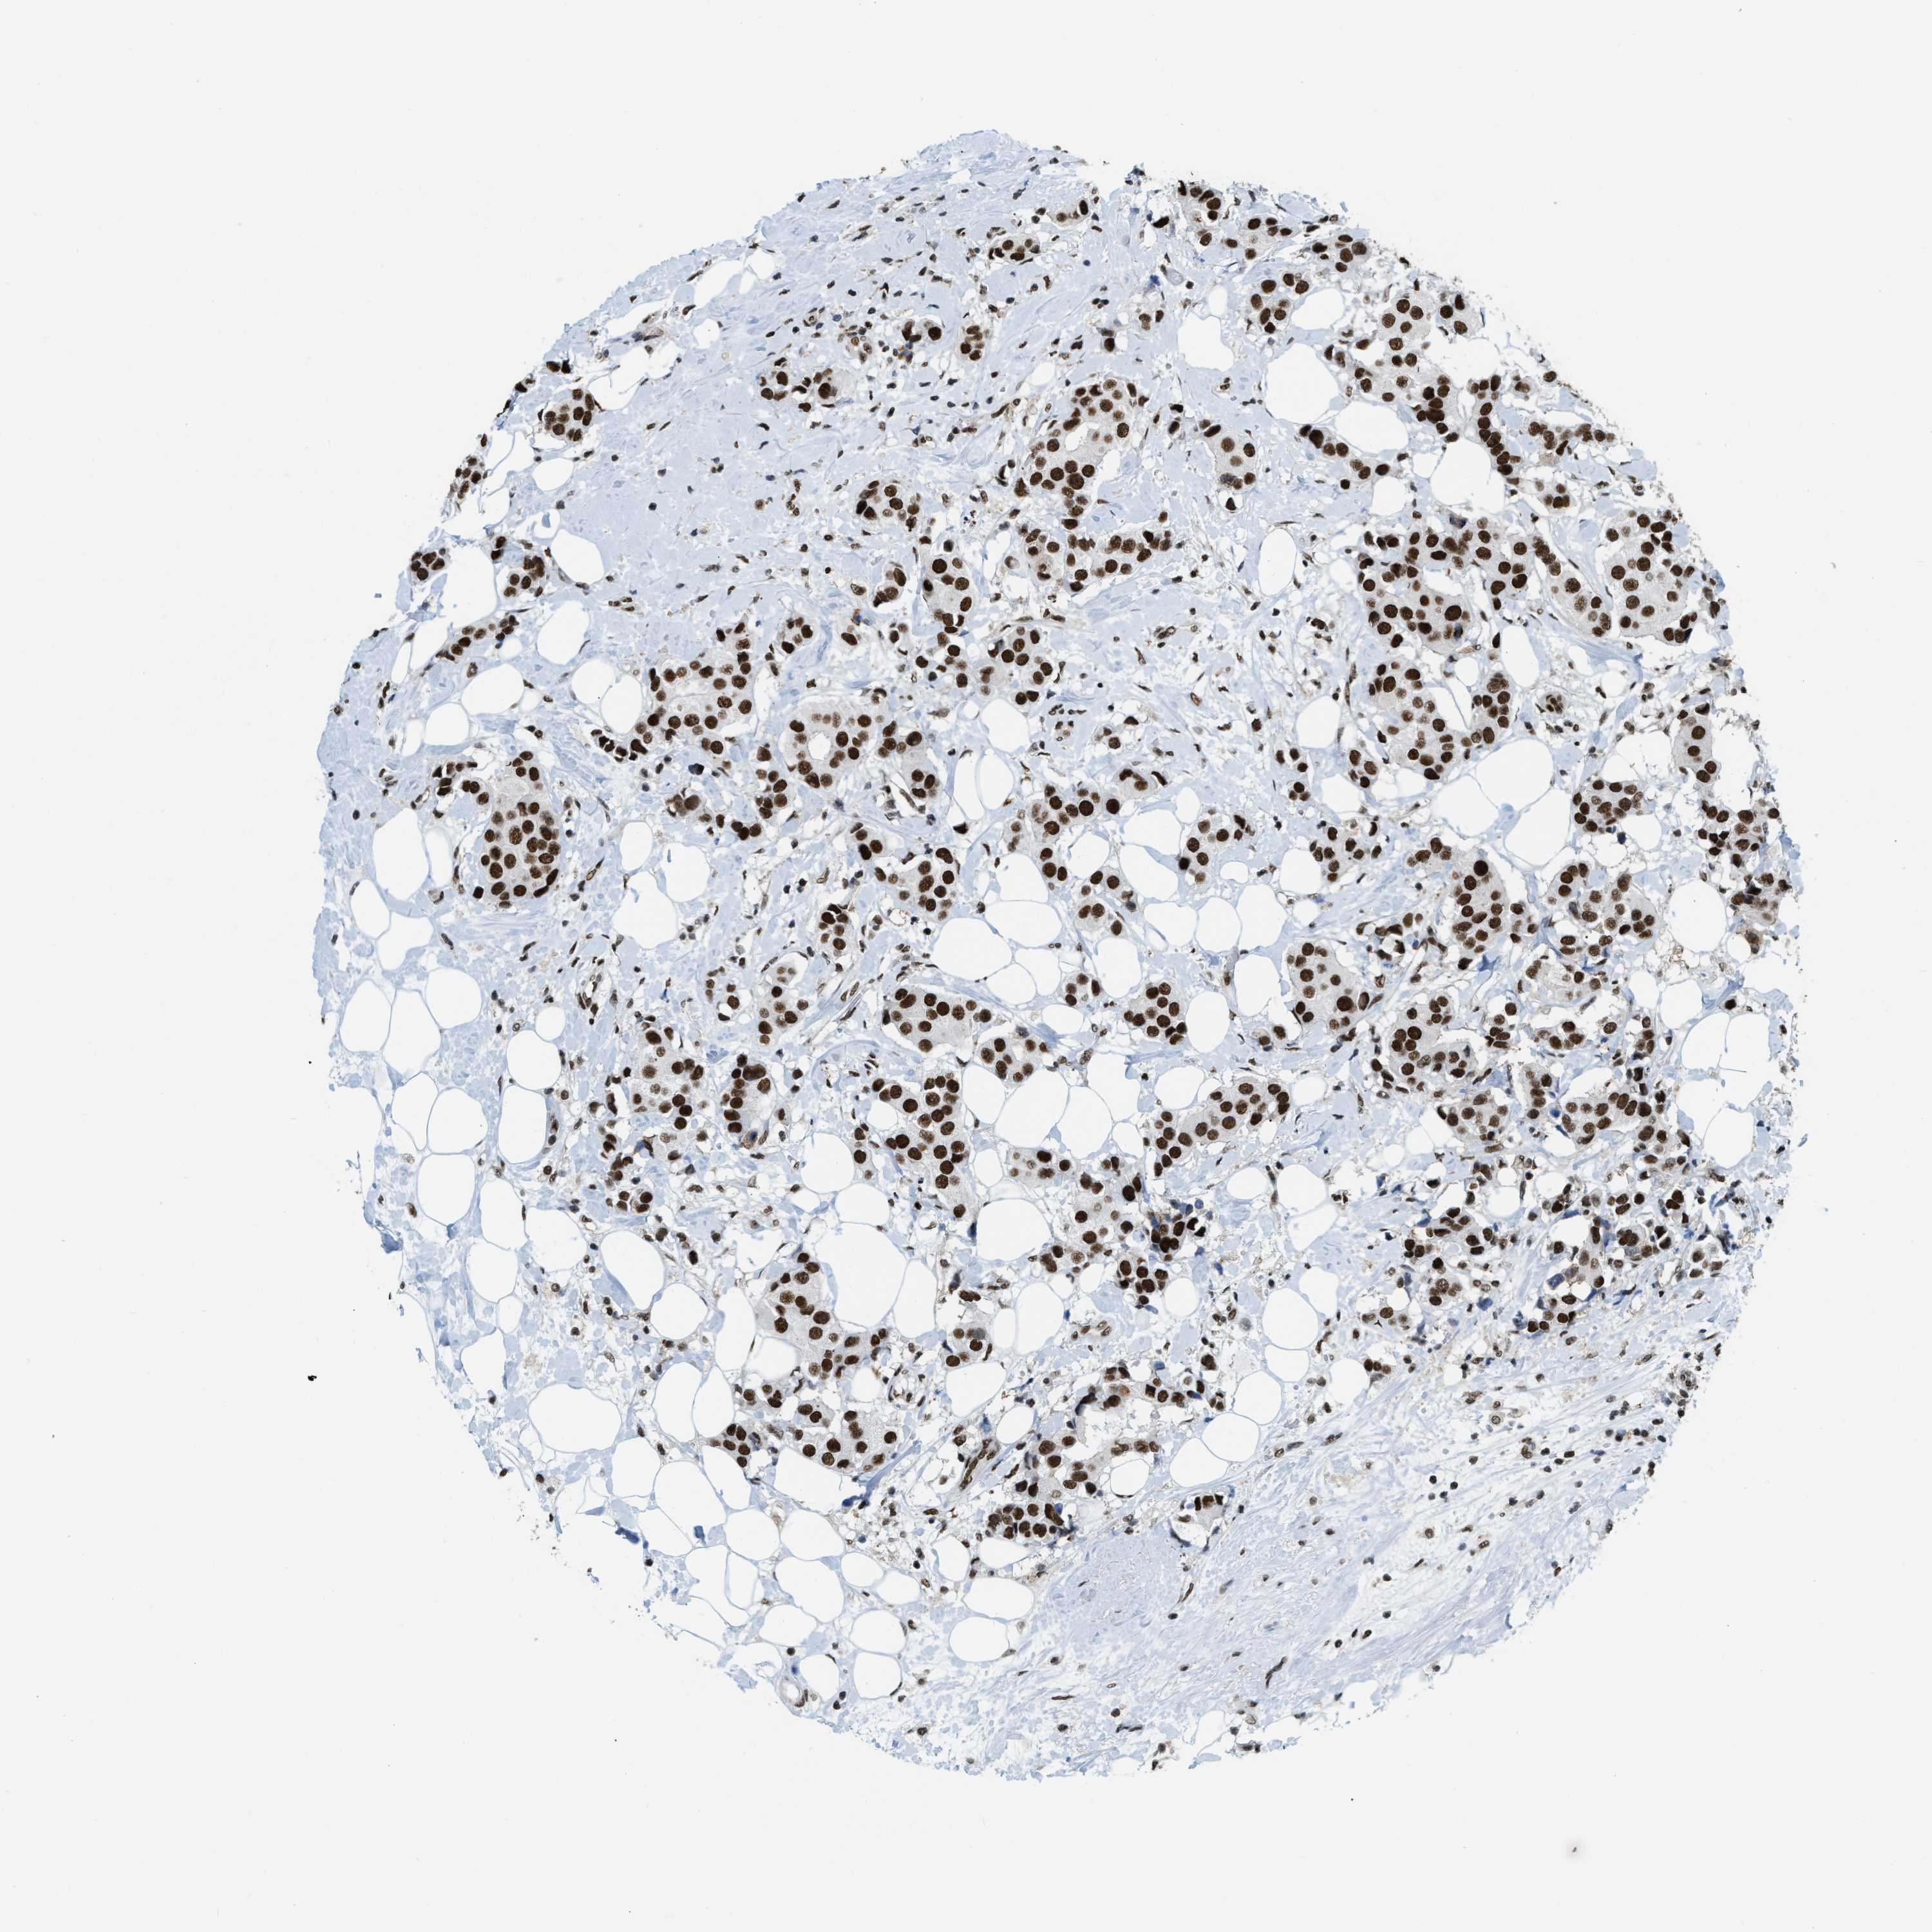

CANCER BREAST CANCER Show tissue menu

BRCA TCGA BRCA VALIDATION PROTEIN EXPRESSION

ANTIBODIES

AND

VALIDATION